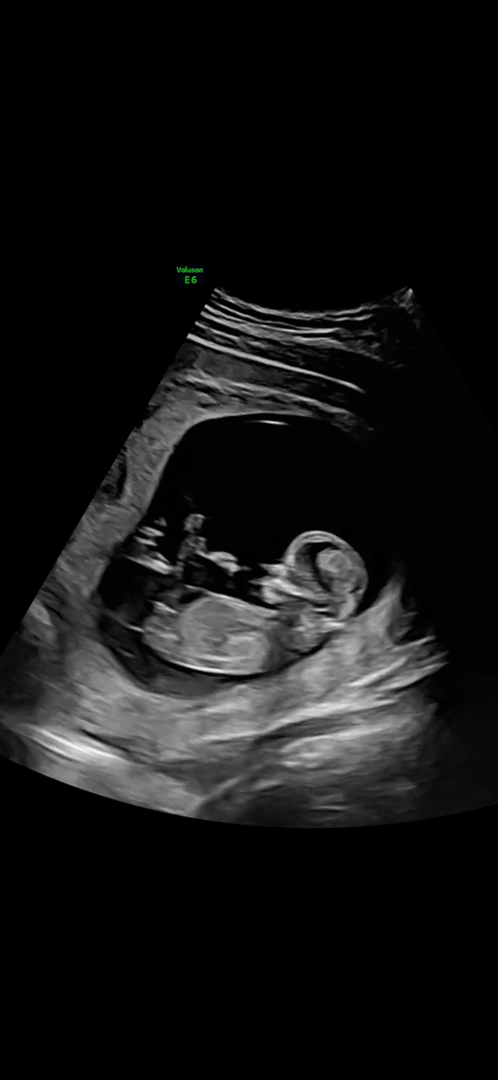

12주 5일 각도법 질문

해외라 사진이 선명하진 않은데 고수님들 투표 한번씩 해주세요! 너무 궁금해요 ㅠㅠ 감사합니다